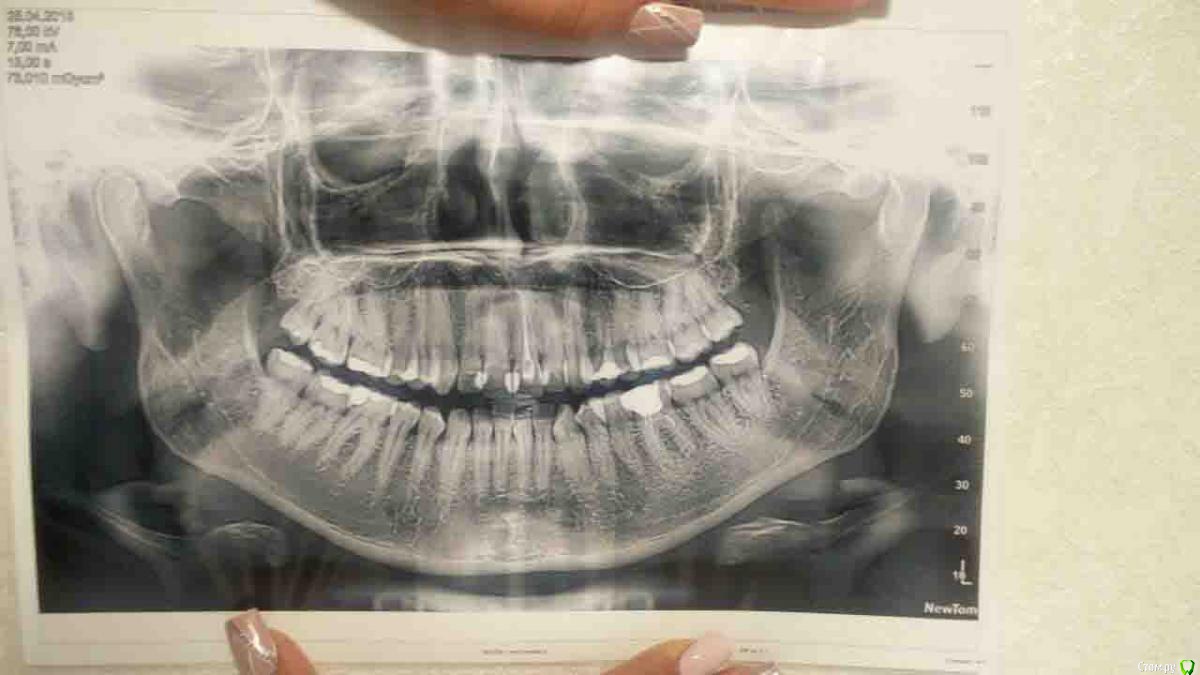

Валг Опубликовано 31 августа, 2018 Поделиться Опубликовано 31 августа, 2018 Добрый день!Нужен совет по поводу исправления прикуса, перекрестный, 3 класс, но точно я не уверена, врач мне мало что разъяснил. Ношу уже 4 месяца, и теперь врач мне говорит что нужно удалять нижние 5, так как они мешают смыканию челюстей и зубы вынуждены сильно наклонятся вперёд.Изначально ортодонт говорил, что удаление зубов не потребуется. Посоветуйте, пожалуйста, что делать! Ссылка на комментарий

Kazankov.Egor Опубликовано 1 сентября, 2018 Поделиться Опубликовано 1 сентября, 2018 Как минимум, я бы сейчас остановился: смущает то, что на ОПТГ (снимок всех зубов) центры зубных рядов более-менее совпадают, скорее всего это проблема зубных контактов, которые имеются на данный момент. Первое - депрограммирование челюсти. По остальному: нужно видеть фото полные внутриротовые и модели "до" и "на этапе". Ссылка на комментарий